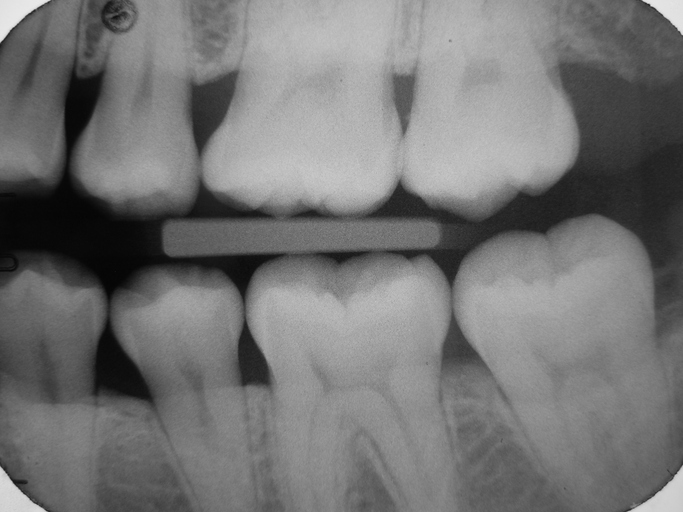

3. 바이트윙 엑스레이

①상하 치아의 교합면(씹는 면)을 동시에 촬영

②용도

●인접면 충치 확인 (치아 사이 충치)

●보철물 상태 확인

●초기 잇몸뼈 흡수 확인